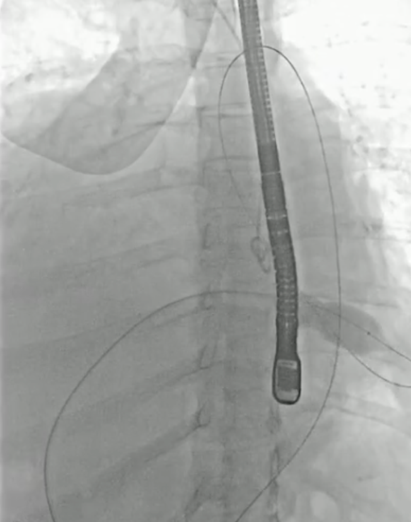

小球囊预扩张

20mm球囊预扩张

双平面造影确认植入位置

释放完成

球囊后扩后,超声确认植入位置合适,形态满意,造影未见反流